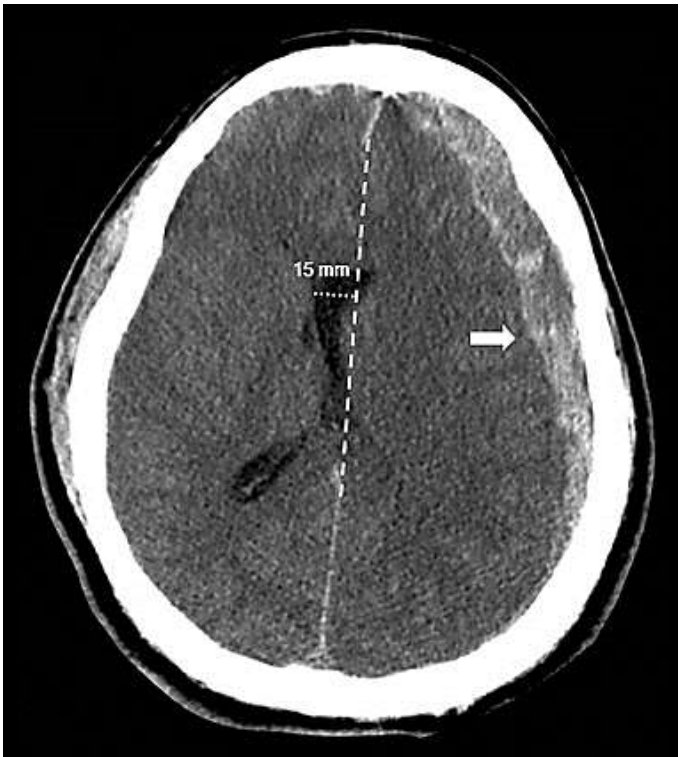

Homem de 75 anos, vítima de queda de 3 metros de altura, seguida de perda de consciência, vômitos e cefaleia. Chega à emergência apresentando-se: sonolento, expressando sons incompreensíveis, respondendo a estímulos verbais (abre o olho quando contactado) e localiza a dor. Pupilas anisocóricas, SO2: 85%, PA: 110 x 75 mmHg.

Sobre o caso anterior, o paciente encaminhado para realização de tomografia de crânio (imagem).

Tomografia de crânio

Sobre o diagnóstico mais provável e a melhor conduta sugerida ao paciente, assinale a alternativa correta.